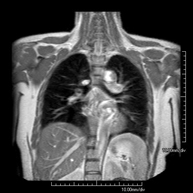

- Thorax

- Mediastinal MRI

This non-invasive diagnostic procedure uses an electromagnetic field and radio waves (from a transmitter and receiver) to acquire high-definition anatomical images of the mediastinum. It is a radiation-free procedure. The mediastinum is the central part of the rib cage that includes the thymus, the great vessels (thoracic aorta, inferior and superior vena cava, etc.), the heart, the trachea and main bronchi, mediastinal and hilar lymph nodes, the oesophagus, etc. It is especially indicated in mediastinal lesions to differentiate between cystic and solid lesions, in the differential diagnosis of anterior mediastinal lesions, etc. Sometimes paramagnetic contrast (gadolinium) must be used to complete the study.